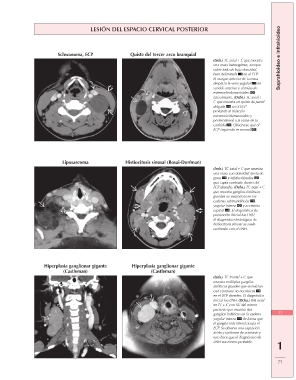

LESIÓN DEL ESPACIO CERVICAL POSTERIOR Suprahioideo e infrahioideo

Schwanoma, ECP Quiste del tercer arco branquial

(Izda.) TC axial + C que muestra

una masa heterogénea, aunque

sobre todo de baja densidad,

bien delimitada en el ECP.

El margen anterior de la masa

desplaza la vena yugular en

sentido anterior y el músculo

esternocleidomastoideo

lateralmente. (Dcha.) TC axial +

C que muestra un quiste de pared

delgada en el ECP

profundo al músculo

esternocleidomastoideo y

posterolateral a la vaina de la

carótida . Obsérvese que el

ECP izquierdo es normal .

Liposarcoma Histiocitosis sinusal (Rosai-Dorfman)

una masa con densidad mixta de

grasa y tejidos blandos

que capta contraste dentro del

ECP derecho. (Dcha.) TC axial + C

que muestra ganglios linfáticos

grandes no necróticos en las

cadenas submandibular ,

yugular interna y accesoria

espinal . El diagnóstico de

presunción inicial fue LNH.

El diagnóstico histológico de

histiocitosis sinusal se suele

confundir con el LNH.

Hiperplasia ganglionar gigante Hiperplasia ganglionar gigante

(Castleman) (Castleman)

(Izda.) TC frontal + C que 71

muestra múltiples ganglios

linfáticos grandes que se realzan 1

con contraste no necróticos

en el ECP derecho. El diagnóstico 71

inicial fue LNH. (Dcha.) RM axial

en T1 + C con SG del mismo

paciente que muestra dos

ganglios linfáticos en la cadena

yugular interna de forma que

el ganglio más lateral ocupa el

ECP. Se observa una captación

ávida y uniforme de contraste y

esto hace que el diagnóstico de

LNH sea menos probable.